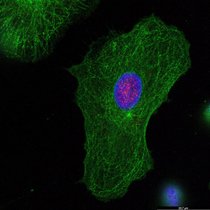

Ein zweistufiger Mechanismus des angeborenen Immunsystems, der es ermöglicht, auch das HI-Virus (Humanes Immundefizienz-Virus, HIV) spezifisch zu…